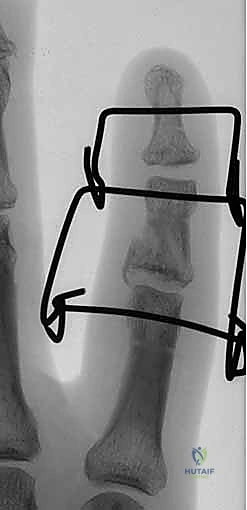

Figures 1A and 1B (TECH FIG 1A,B) show us marking the position for the first wire at the level of the center of rotation of the PIP joint, confirmed with the image intensifier.

-

Determine Entry Point: Aim to insert the wire 1 to 2 mm proximal to the marked center of rotation.

> SURGICAL WARNING: Aiming slightly proximal is crucial. The joint capsule reflects proximally from the articular margin. By staying 1-2mm proximal, we ensure the wire remains extracapsular. A distal wire, penetrating the joint capsule, significantly increases the risk of joint infection if pin track sepsis develops, leading to catastrophic outcomes. Conversely, placing this wire too far proximally in the diaphysis of the proximal phalanx will restrict full joint movement, defeating the purpose of a dynamic fixator. This balance is key. -

Initial Wire Insertion: Take your 1.1-mm K-wire and, under direct visualization and fluoroscopic guidance, initiate insertion through the skin and subcutaneous tissue. Aim for the center of the proximal phalanx in both PA and lateral planes. Ensure it is perpendicular to the long axis of the finger and parallel to the intended plane of rotation of the joint.

> PEARL: As you insert, you should feel the resistance of the cortical bone. Advance slowly, using a drill with a controlled, oscillating motion to prevent thermal necrosis of the bone. -

Fluoroscopic Confirmation (Partial Insertion): Insert the wire partially through the proximal phalanx, ensuring it crosses the head of the proximal phalanx. Immediately check its position with both true posteroanterior (PA) and lateral projections on the image intensifier.

Figure 1C (TECH FIG 1C) confirms the wire inserted across the head of the proximal phalanx, verified on the image intensifier, before further advancement.

- Finalize Proximal Wire Placement: Once confirmed, advance the wire fully through the bone, ensuring equal lengths are present on either side of the finger. This symmetry, while less critical for the proximal wire, will serve as a useful guide for balancing the distal wire later.